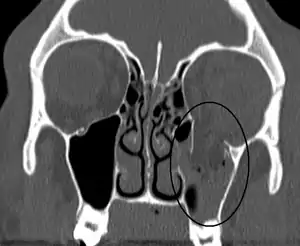

| An orbital blowout fracture of the floor of the left orbit. | |

Thin cut (2-3mm) CT scan with axial and coronal view is the optimal study of choice for orbital fractures.[8][11]